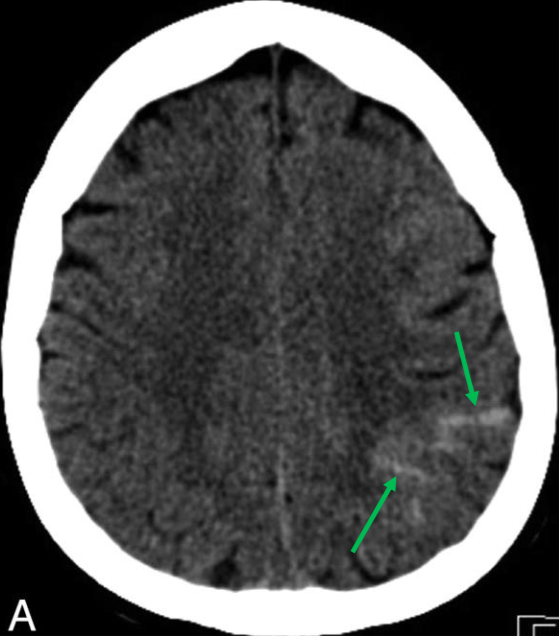

蛛網膜下腔出血 (SAH)

image